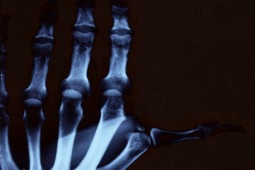

Początkowo uważano, iż aktywność fizyczna jest niekorzystna dla chorych z reumatoidalnym zapaleniem stawów (RZS). Tymczasem przeprowadzone badania interwencyjne dowiodły jednoznacznie, iż aktywność fizyczna jest dla chorych z RZS bezpieczna, a co więcej korzystnie wpływa na przebieg choroby. Aktywność fizyczna działa poprzez różne ścieżki patomechanizmu RZS na obniżenie parametrów stanu zapalnego.

Celem badania było określenie, czy regularna aktywność fizyczna przed zachorowaniem na RZS ma wpływ na późniejszy przebieg choroby. Wykorzystano dane z populacyjnego badania przeprowadzonego w Szwecji (badanie EIRA, n=671). Aktywność fizyczna była oceniana na podstawie kwestionariusza w skali 4 stopniowej oraz w skali dychotomicznej (aktywny/nieaktywny) w okresie 5 lat przed rozpoznaniem choroby.

Wykazano, że im wyższa była aktywność fizyczna pacjentów przed zachorowaniem tym mniejsze było ryzyko uzyskania wyników aktywności choroby w chwili rozpoznania powyżej średniej. Regularna aktywność fizyczna była związana z 42% zmniejszeniem ryzyka uzyskania wartości DAS 28 powyżej średniej. Podobne wyniki zależności uzyskano dla oceny aktywności choroby przez lekarza oraz dla skali bólu ocenianej przez pacjenta (VAS-pain, wizualna analogowa skala oceny bólu).